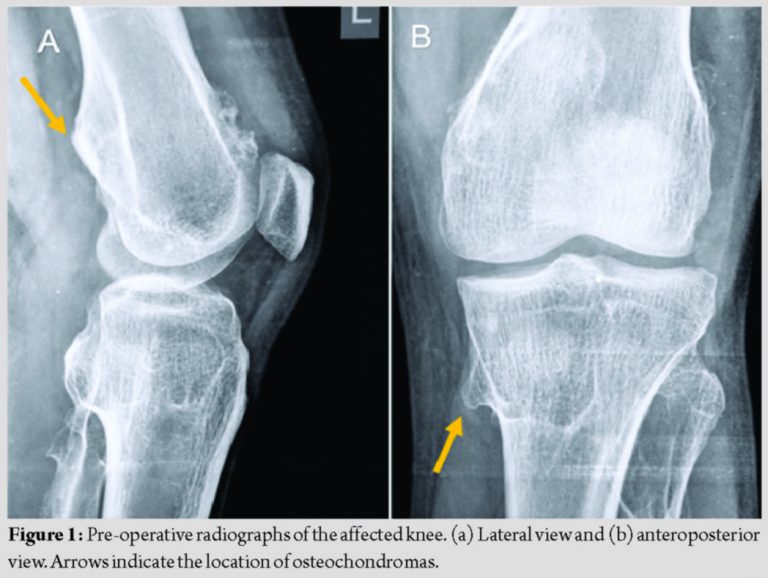

Radiographs of the knee revealed bony swellings of the left proximal tibia and left distal femur, which suggested osteochondromas (Fig. 1). Radiographs of other joints revealed osteochondromas of both ankles and shoulders (Fig. 2). MRI of the left knee revealed a bucket handle tear involving the posterior horn and body of the medial meniscus. A complete tear of the ACL is shown in Fig. 3. The diagnosis of osteochondroma was also confirmed on MRI.